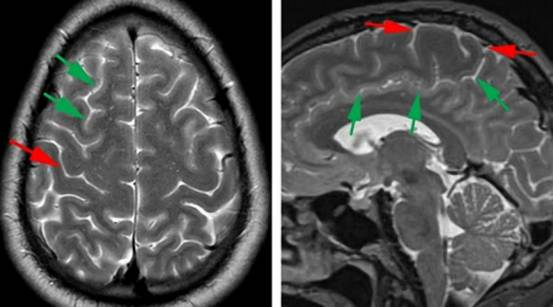

术前影像学检查有助于确定是否要行运动功能区定位。术前使用MRI可以对感觉运动功能区进行解剖定位,中央小叶的影像学定位比语言皮层区的定位更可靠。长期生长的病变如皮质发育不良、脑动静脉畸形和神经节细胞胶质瘤可能会引起功能区移位。

图1. 中央沟的影像学标志。源自于额上沟(绿色箭头)水平部末端向后的第二条垂直脑沟的是中央沟(红色箭头)(左图)。更多可靠的定位方法如下:先在正中矢状位MRI找到扣带沟(绿色箭头),然后向上(边缘沟)直至大脑边缘。边缘沟位于Rolandic区(中央小叶:红色箭头包绕区)后方,(右图)。